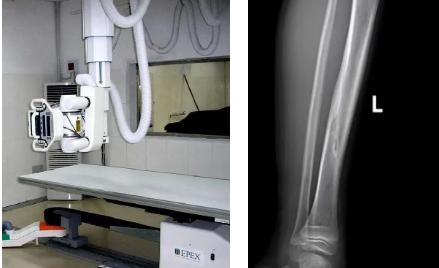

一般骨科創(chuàng)傷的病人,只要到影像科拍一張X光片,很快就會明確診斷有沒有骨折。然而有一些特殊類型骨折的病人,由于拍片影像重疊的緣故,或者骨折未發(fā)生明顯移位,病變可能顯示不出來,等過了一段時間后,骨折部位才能夠顯示清楚。這種類型的骨折,叫做隱匿性骨折。若在臨床上診斷及時且明確,及時固定患者的骨折部位,進行適當治療并減少運動,對患者的恢復有重要意義。

1.定期復查。一般于骨折后2-4周,骨折進入骨痂期,骨折斷端有新生骨形成,呈明顯高密度,無論是X線或是CT,都能比較清晰觀察到,通過前后圖像對比,較容易診斷隱匿性骨折。

2.CT或MRI檢查。CT是斷面成像,不會出現(xiàn)重疊而導致漏診,同時CT還可以進行多平面的重建,除了發(fā)現(xiàn)X線無法發(fā)現(xiàn)的骨折外,還可以三維直觀的顯示骨折的程度,對臨床治療有指導意義。CT無法發(fā)現(xiàn)骨裂、不全骨折或者骨挫傷,對軟組織的損傷診斷也有局限性,MRI就可以發(fā)現(xiàn)這些損傷。